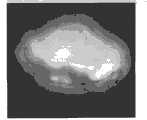

图5为肿瘤形状大小以及到各管道系统最短距离图;Figure 5 is a diagram of the shape and size of the tumor and the shortest distance to each pipeline system;

(1)对肿瘤大小、最大径以及肿瘤表面到各管道系统距离的计算及可视化。参见图5,肿瘤大小,形状,最大径及表面各点到肝静脉,肝动脉,门脉,胆囊各管道系统的最短距离可通过该设备精准的反映与测量出来。(1) Calculation and visualization of the tumor size, maximum diameter, and distance from the tumor surface to each pipeline system. See Figure 5, the tumor size, shape, maximum diameter, and the shortest distance from each point on the surface to the hepatic vein, hepatic artery, portal vein, and gallbladder piping system can be accurately reflected and measured by this device.